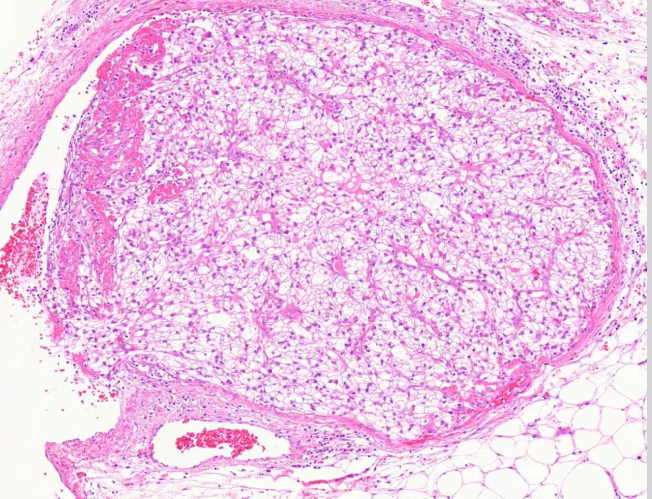

Kirkassoluinen munuaiskarsinooma

MIKÄ TAUTI? Kasvaimen vaskulaari-invaasiota perirenaalisessa rasvakudoksessa.